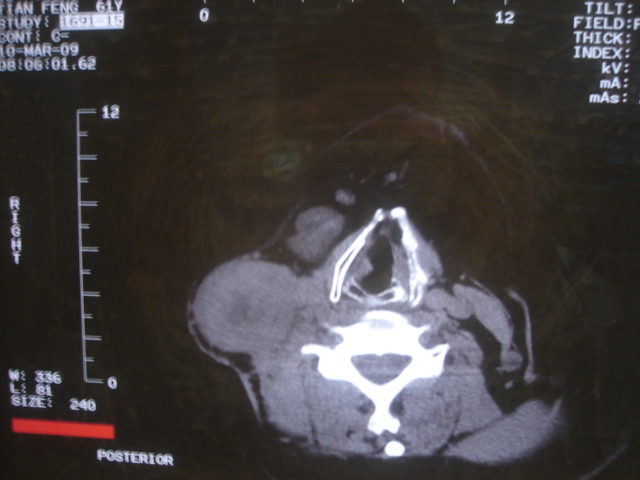

患者 男 61  甲状腺ca术后7年 颈部淋巴结转移

声门下区表面不光整,增厚呈局限性突起,未见局部浸润.

考虑----颈部淋巴结转移,不排除---喉乳头状瘤可能.

另声门区不规则突起,建议喉镜检查!

右侧颈部淋巴结转移,右声带乳头突起,乳头状瘤可能性大。

1)右侧颈部淋巴结转移瘤。2)右侧声带新生物,性质待定;建议喉镜检查(活检)。